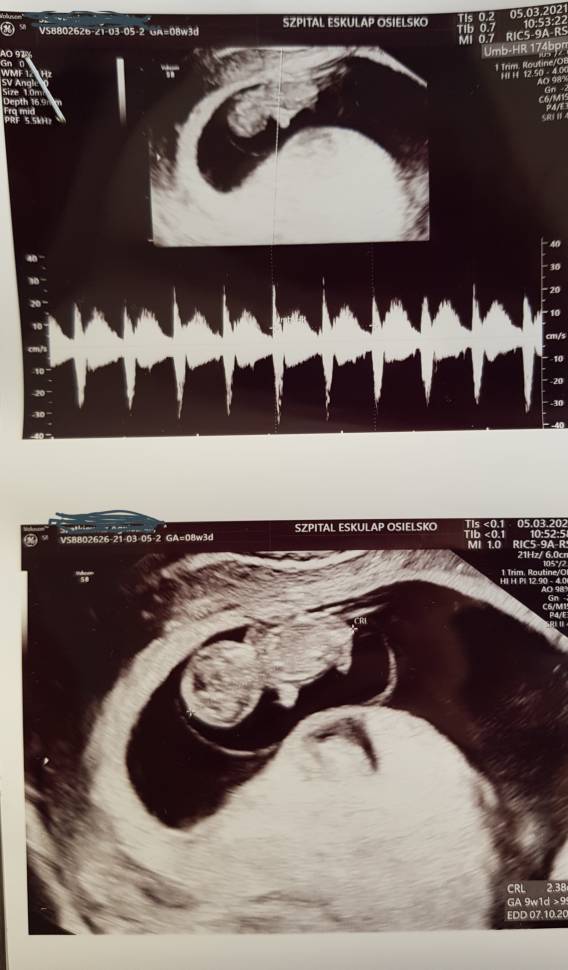

Ale piękne, duże Bobo!Po wizycie. Rośniemy zdrowo [emoji3060] Ten stres mnie wykończy. Nie śpię od 1 w nocy. Zobacz załącznik 1244986

PiękniePo wizycie. Rośniemy zdrowo [emoji3060] Ten stres mnie wykończy. Nie śpię od 1 w nocy. Zobacz załącznik 1244986